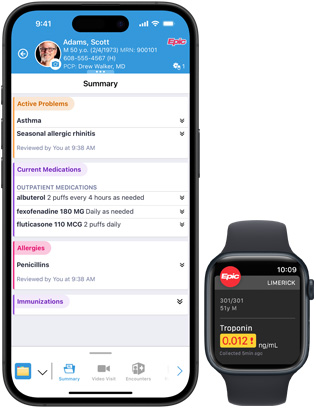

Epic Haiku and Limerick on iPhone and Apple Watch give authorized clinicians secure access to patient records from iPhone. Real-time updates and notifications can be displayed on iPhone and Apple Watch with Epic Limerick.